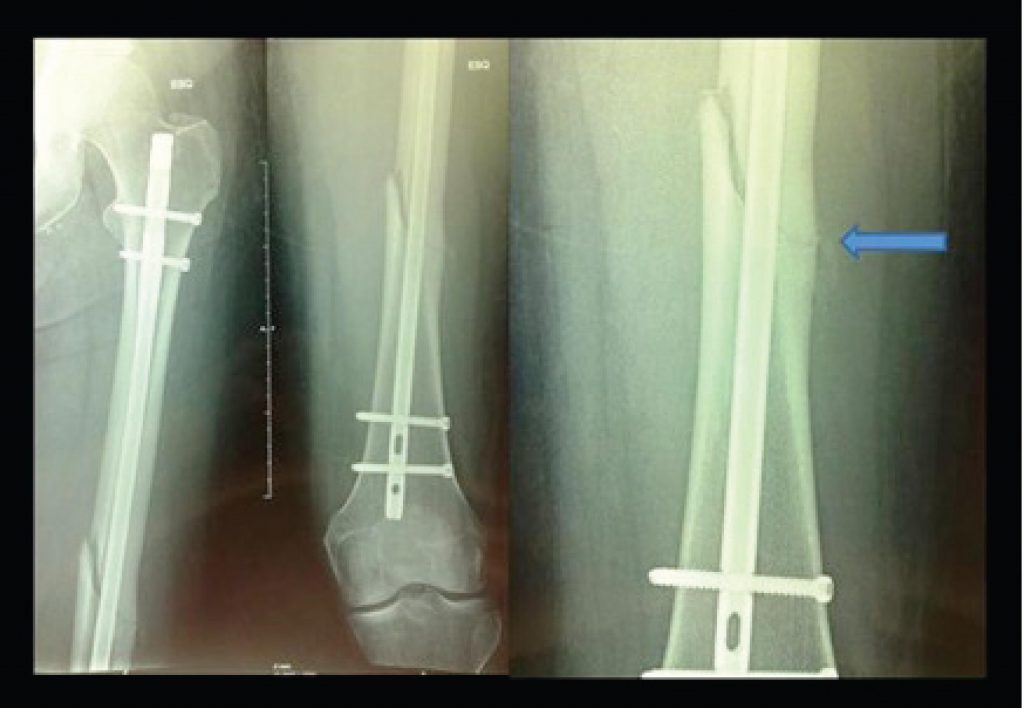

Low-energy femoral shaft fracture in elderly patient with prolonged use of alendronate

Fractures in the proximal femur occur in female and male elderly population due to low-energy trauma in osteoporotic bones. In order to prevent these fractures, treatment of osteoporosis has been indicated, particularly using biphosphonates().

Alendronate was the first drug approved by the Food and Drug Administration (FDA), in 1995, to treat osteoporosis(). This drug acts in bone metabolism, inhibiting osteoclasts, inducing their apoptosis(), raising the bone mineral density and reducing the incidence of osteoporotic fractures().